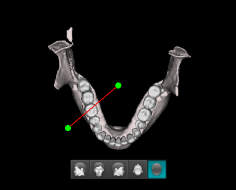

Сегментация зубов и костей

Автоматическое отделение зубов от костей и тела нижней челюсти от верхней челюсти выполняется модулем Segment. При необходимости данные о поверхности можно экспортировать* из программы Ez3D-i в виде отдельных файлов STL.

* При экспорте исследования в программу просмотра данные КТ записываются на диск вместе с моделями зубов и челюстей.

Сегментация зубов

Сегментация кости

Виртуальное удаление зубов

Функция виртуального удаления зубов позволяет проводить планирование функционального ортодонтического лечения без необходимости удаления зубов.

Приятным бонусом к ортодонтическим возможностям сегментации является виртуальное удаление зубов при планировании операции имплантации.